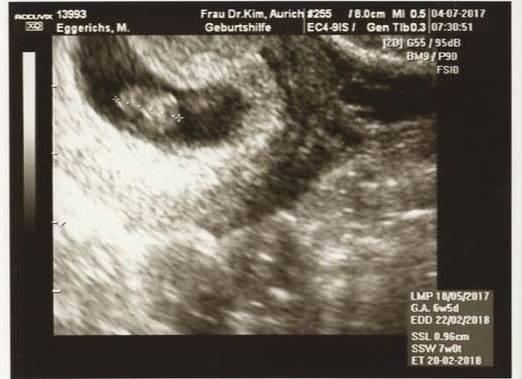

Das kleine herzchen schlägt und das kleine ist 0.96 cm gross jetzt hab ich erstmal eine menge lesestoff von der fa mitbekommen der muttetpass wurde angefangen blut würde abgenommen sobald die werte da sind und eingezragen sind bekomme ich den mutterpass mit

Am 4.8 ist der nächste termin ja habr och

Bild zu